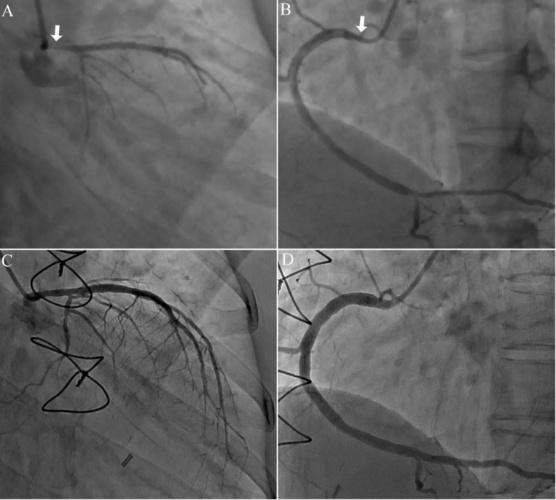

图13 导管诱发左主干开口痉挛,误搭桥。

36岁女性拟行房缺介入封堵,术前诉活动后胸闷气促,冠脉造影发现左主干开口狭窄95%,右冠开口狭窄70%伴导管压力嵌顿,患者转外科行房缺补片修补,同时LIMA-LAD搭桥手术。5年后复查造影惊奇的发现冠脉开口狭窄消失!回顾性诊断导管诱发冠脉痉挛。

图14 导管诱发左主干开口痉挛【14】

左主干开口狭窄90%,患者拒绝CABG[4],次日拟行PCI治疗。再次造影发现狭窄消失,考虑导管诱发痉挛,再次造影避免了不必要的CABG手术。

图15 导管深插诱发右冠口痉挛。

JR4造影导管头端刺激右冠开口痉挛(A),稍回撤注射硝酸甘油后缓解(B)。